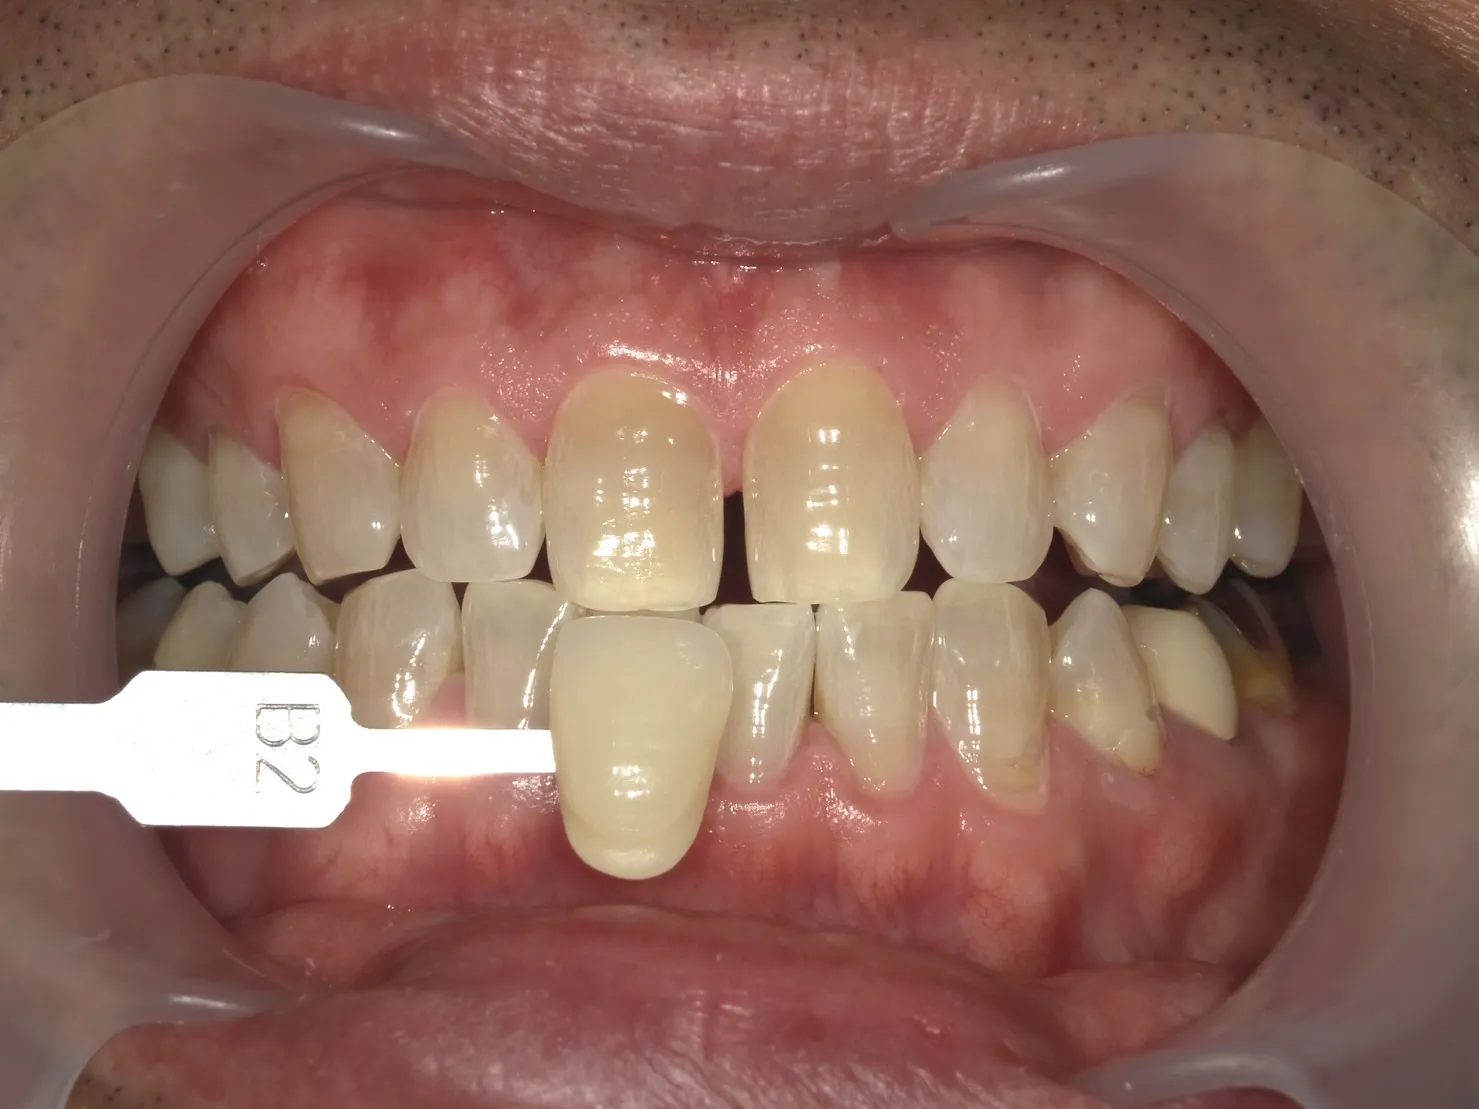

テトラサイクリン歯とは

テトラサイクリン歯とは、テトラサイクリン系抗生物質の服用によって引き起こされる歯の着色の一種です。

この状態は、特に幼少期にこの薬を服用した場合に見られることが多く、歯の発達に影響を与えることが知られています。

テトラサイクリン歯の特徴

深い着色

テトラサイクリン歯は、黄色から茶色、時には灰色の着色を示すことがあります。

この着色は歯の表面だけでなく、内部にまで及ぶことが特徴です。

不均一な着色パターン

テトラサイクリン歯の着色は歯全体に均等に現れるわけではありません。

歯によってはバンド状、斑点状、または不規則なパターンで現れることが特徴です。